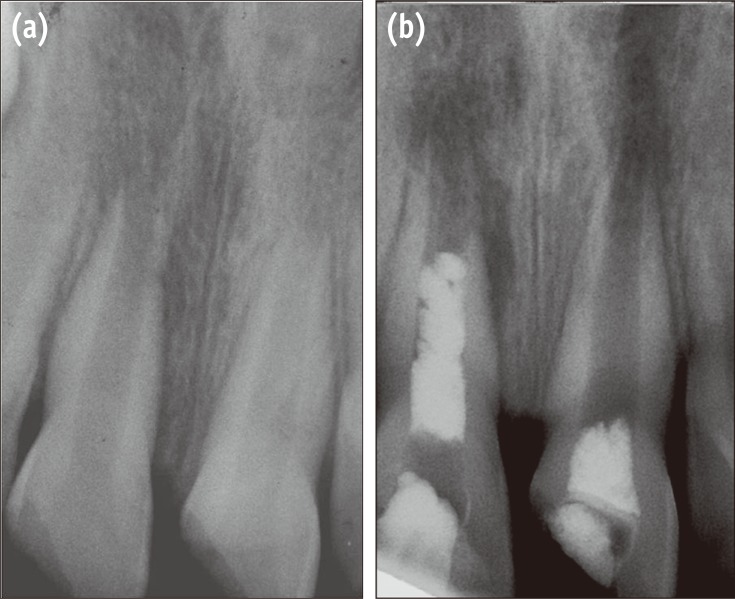

A 9-year-old boy was referred to the Department of Endodontics with pain on chewing and localized swelling on the anterior region of maxilla and a history of prior impact trauma three months previously. His medical history was non-contributory. Clinical examination showed complicated crown fracture on both maxillary central incisors. A large pulpal exposure, sensitivity to palpation and percussion and also localized swelling on the buccal mucosa of the right central incisor was observed. Cold thermal test elicited no response in this tooth. Left central incisor with a pinpoint pulpal exposure had no sensitivity in periapical tests and showed lingering painful response to cold test. Radiographic examination revealed that the fractured teeth had immature apices, and a radiolucent periapical lesion was observed adjacent to the right central incisor (Figure 1a). Based on clinical and radiographic examinations, the definitive diagnosis was irreversible pulpitis in the left central incisor and pulpal necrosis with symptomatic apical abscess in the right central incisor. Considering the immaturity of the teeth, the first treatment option was vital pulp therapy for the left central incisor and revascularization of the right one.

Under local anesthesia with 2% Lidocaine and 1 : 800,000 epinephrine (Xylocaine 2%, Dentsply, Addlestone, UK) and rubber dam isolation, an access cavity was prepared for the left central incisor. Coronal pulp tissues were removed by using a high-speed sterile long shank round diamond bur under copious water spray. The area was rinsed with normal saline solution and hemostasis was achieved by a cotton pellet moistened with 5% sodium hypochlorite (NaOCl). White Mineral Trioxide Aggregates (ProRoot MTA, Dentsply, Tulsa, OK, USA) powder was mixed with distilled water according to manufacturer's instructions and placed without pressure over the exposed clot-free pulpal wound (Figure 1b). The material was gently patted down with a moist cotton pellet. Then a moistened cotton pellet was placed over MTA and the tooth was temporarily filled with Cavit (Asia Chemi Teb Co., Tehran, Iran). One day later, the teeth were restored permanently with composite resin (Filtek Z350, 3M ESPE, St. Paul, MN, USA).

An access cavity was prepared for the right central incisor using the same procedure. On entering the pulp chamber, purulent drainage was observed. Length was estimated radiographically using a size #15 K-file (K-file, Mani Corp., Tokyo, Japan). The canal was passively irrigated with 20 mL of 5.25% NaOCl and gently dried with paper points. A creamy mixture of equal proportions of ciprofloxacin, metronidazole and minocycline, as described by Hoshino et al., was placed in the root canal with a #25 K-file up to 3 mm short of the radiographic apex.10 The access cavity was sealed temporarily with Cavit. After 3 weeks the patient was asymptomatic and the localized swelling had resolved. The tooth was anesthetized with a local injection of 3% plain Mepivacaine (Septodont, Cedex, France) without vasoconstrictor. After rubber dam isolation and removal of Cavit dressing, the antibiotic dressing material was removed by irrigation with 10 mL of 5.25% NaOCl and saline. The canal was then dried with paper points. A #40 K-file was used to irritate the apical tissues to create some bleeding into the root canal. The bleeding was allowed to reach the middle part of the canal. Ten minutes later, after the formation of a blood clot, white MTA was mixed and placed over the clot carefully (Figure 1b). A moistened cotton pellet was placed over MTA and the tooth was restored temporarily with Cavit. One day later the patient was referred for permanent restoration of this tooth.